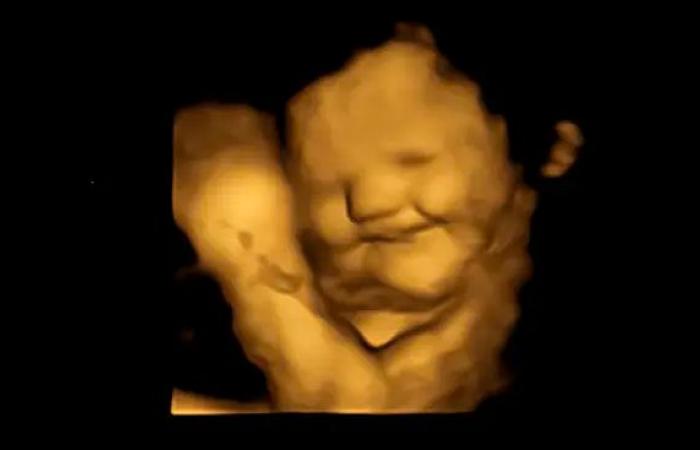

Τα έμβρυα δημιουργούν ένα «χαμογελαστό πρόσωπο» όταν εκτίθενται στη γεύση των καρότων που καταναλώνει η μητέρα τους και δημιουργούν έναν «μορφασμό» όταν εκτίθενται στο λάχανο, σύμφωνα με μια μελέτη που δημοσιεύτηκε στο περιοδικό «Psychological Science».

Ενώ η γεύση καρότου μπορεί να περιγραφεί ως «γλυκιά» από τους ενήλικες, το λάχανο επιλέχθηκε επειδή μεταφέρει περισσότερη πικρία στα βρέφη από άλλα πράσινα λαχανικά όπως το σπανάκι, το μπρόκολο ή τα σπαράγγια, σύμφωνα με τη μελέτη. Μετά από μια περίοδο αναμονής 20 λεπτών μετά την κατανάλωση, οι γυναίκες υποβλήθηκαν σε σαρώσεις 4D υπερήχων, οι οποίες συγκρίθηκαν με 2D εικόνες των εμβρύων.

Το τράβηγμα της γωνίας των χειλιών, που υποδηλώνει χαμόγελο ή γέλιο, ήταν σημαντικά υψηλότερο στην ομάδα καρότου σε σύγκριση με την ομάδα λάχανου και ελέγχου. Ενώ κινήσεις όπως το σήκωμα του άνω χείλους, το ρίξιμο του κάτω χείλους, το πάτημα των χειλιών και ένας συνδυασμός αυτών –που υποδηλώνουν ένα πρόσωπο που κλαίει– ήταν πολύ πιο συνηθισμένες στην ομάδα του λάχανου.